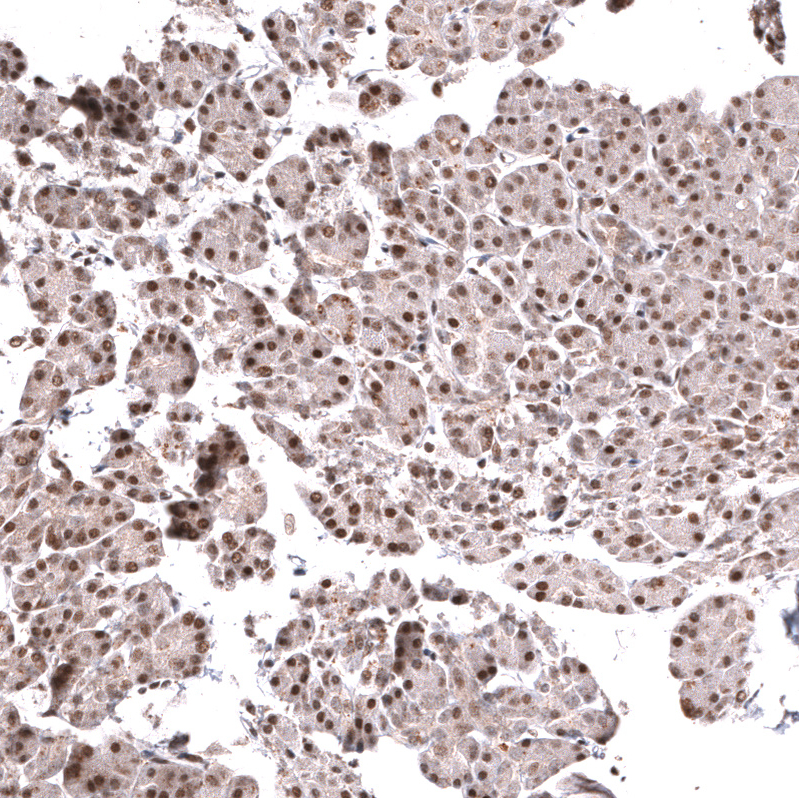

Immunohistochemical staining of human anaplastic oligodendroglioma shows strong nuclear positivity in tumor cells.